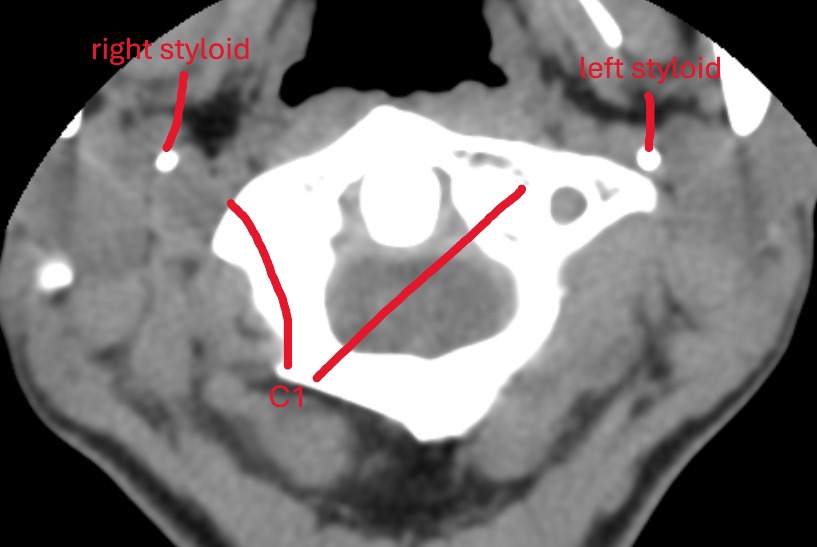

This is the image you attached earlier of your C1 in the axial view:

your styloids are a safe distance from C1 with lots of room for the IJVs and nerves

and then here is the CT scan from this year (I think this month?) of your C1 and styloids:

Your C1 is pointed the opposite direction and the styloid is essentially making contact with C1.

I’ll be honest now that I am seeing just how much a C1 can shift with CCI/AAI, I do wonder the implications of removing a styloid. But either way, you don’t want a styloid smashing against C1. So I’m not sure if craniocervical fusion or other CCI treatments have been discussed with you? The problem some people run into with fusion is that when the fusion happens sometimes the styloids are too close to C1 afterwards and in a fixed position. I have seen cases where people have gotten both fusions and styloidectomies and I wonder if this would be appropriate for you or not. I am not a doctor or radiologist but this difference in C1 positioning and in turn styloid positioning has really intrigued me.

Oh gotcha. It still surprises me that a head turn can close the styloid-C1 distance that much. I do wonder if your CCI/AAI exaggerates the distance changes. I think it must since loose ligaments would increase the amount of mobility of C1 and thus bring it closer to the styloids in certain head positions.

Because even if your head was twisted that much movement I don’t think is normal. If that were the case, I think there would be A LOT more people in this forum because everyone would be smashing their styloid off of C1 and nerves/IJVs with every head turn